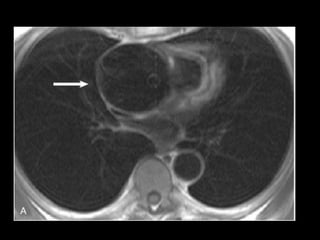

Haaga JR, Dogra VS, Forsting M, et al. TC e RM uma abordagem do corpo humano completa. Editora Mosby-Elsevier, 2009.